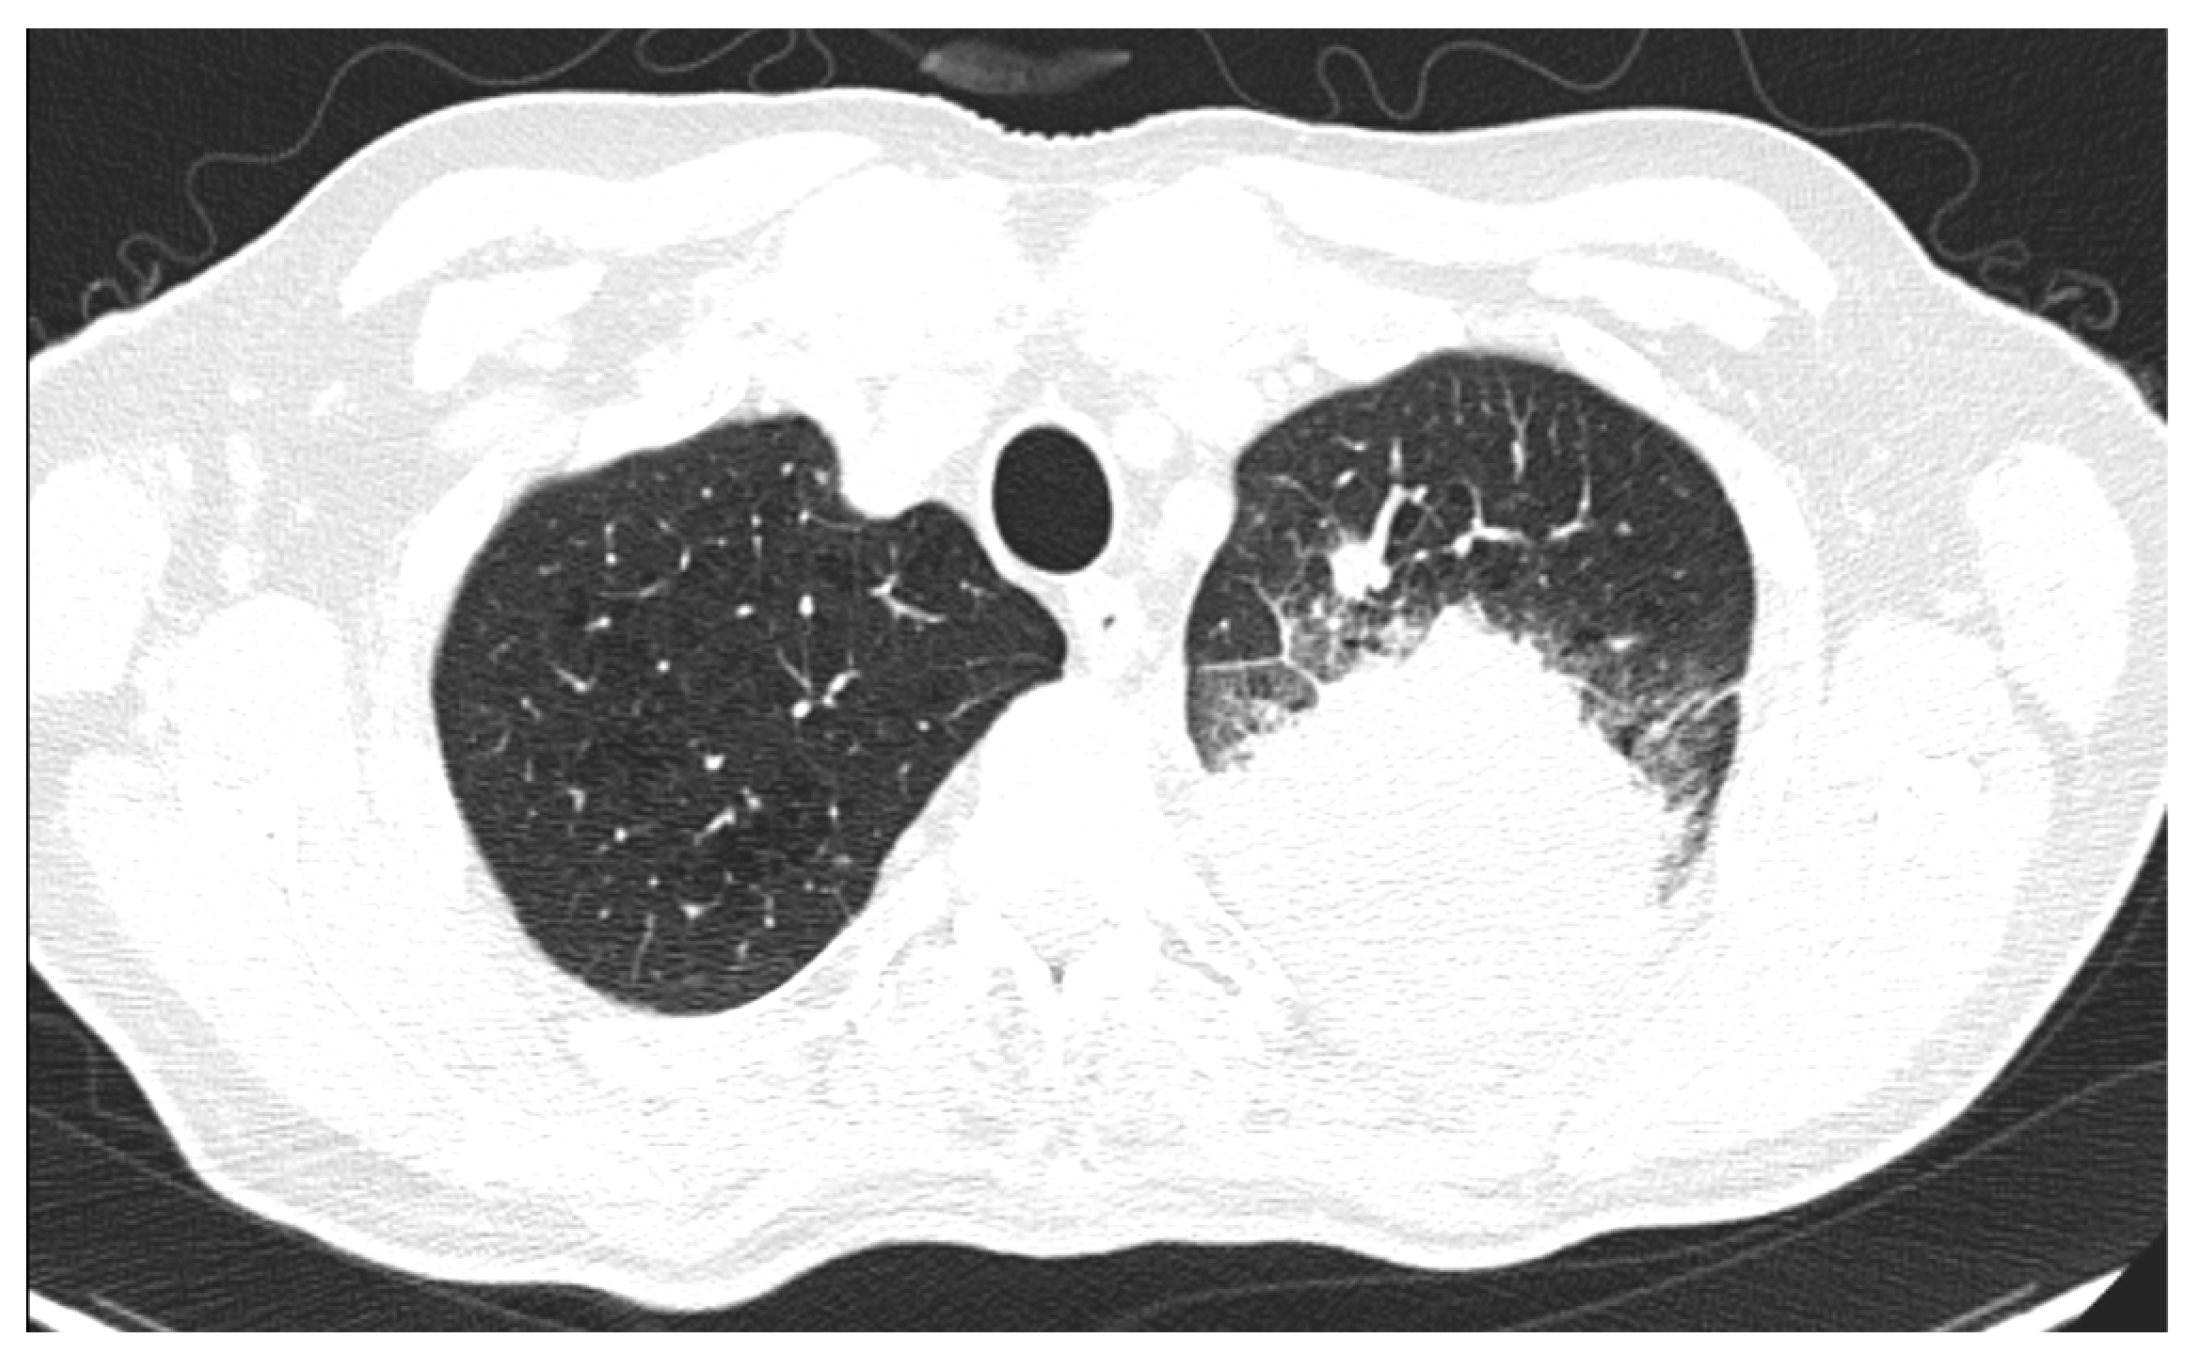

Considering the exclusion criteria previously mentioned, a total of 58 patients were analysed in this study, in which 26 cases were pathologically proven to be adenocarcinoma (Figure 1), 22 cases were shown to be squamous cell carcinoma (Figure 2), and 10 cases were shown to be small cell lung cancer (Figure 3).

Figure 1.

Axial CT of two different cases of adenocarcinoma: (A) a right peripheral mass (the maximal tumoral diameter over three centimetres) with spiculated margins, a small atelectatic area and hilar invasion is highlighted on lung window; (B) soft-tissue window that shows the same tumour as (A) with central necrosis and pleural invasion, including the main right bronchus; and (C,D) a peripheral mass with adjacent pneumonitis in the left lower lobe.